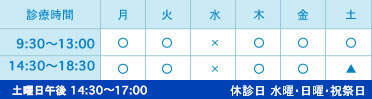

術前は根分岐部から根尖相当部付近にまでおよぶ骨欠損があり、動揺度3度だった歯周病罹患歯が歯周組織再生療法によって、根分岐部付近にも歯根膜空隙用透過像が確認できており、歯根膜再生の可能性を示唆している。

現在、術後6か月経過しているが、動揺もなく、安定した状態で咬合に寄与している。